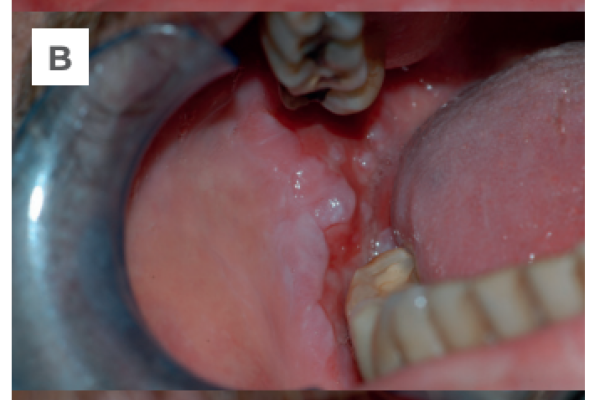

Diagnóstico precoz del carcinoma mucoepidermoide. A propósito de un caso clínico